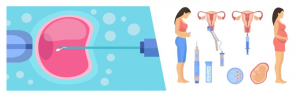

我们协助您做出正确的决定,促进选择阿尔巴尼亚卵子捐赠者的过程,并与卵子库联络以确保捐赠卵子的转移。 当准妈妈由于某些原因无法使用自己的卵子时,卵子捐赠会大有裨益。此外,这对在阿尔巴...

如果准妈妈无法使用自己的卵子进行代孕,您可能需要在英国的卵子捐赠者。此外,如果准父母有将一些严重的健康问题遗传给未来孩子的风险,他们可以使用该国的卵子捐赠者的服务。 尽管如此,在进...